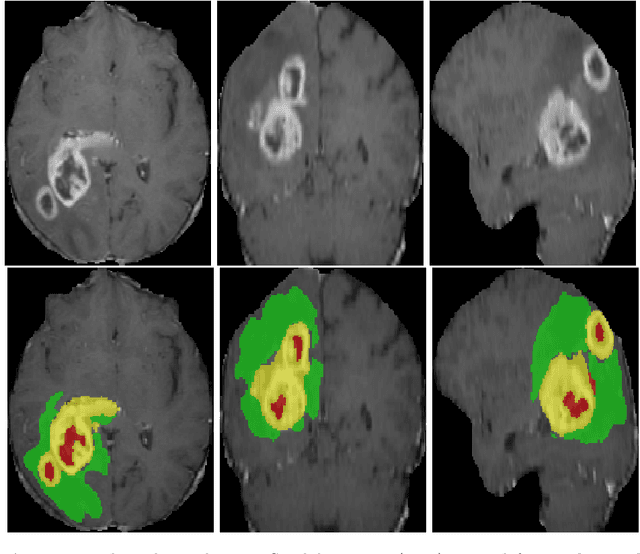

Abstract:Over the last decade, convolutional neural networks have emerged and advanced the state-of-the-art in various image analysis and computer vision applications. The performance of 2D image classification networks is constantly improving and being trained on databases made of millions of natural images. However, progress in medical image analysis has been hindered by limited annotated data and acquisition constraints. These limitations are even more pronounced given the volumetry of medical imaging data. In this paper, we introduce an efficient way to transfer the efficiency of a 2D classification network trained on natural images to 2D, 3D uni- and multi-modal medical image segmentation applications. In this direction, we designed novel architectures based on two key principles: weight transfer by embedding a 2D pre-trained encoder into a higher dimensional U-Net, and dimensional transfer by expanding a 2D segmentation network into a higher dimension one. The proposed networks were tested on benchmarks comprising different modalities: MR, CT, and ultrasound images. Our 2D network ranked first on the CAMUS challenge dedicated to echo-cardiographic data segmentation and surpassed the state-of-the-art. Regarding 2D/3D MR and CT abdominal images from the CHAOS challenge, our approach largely outperformed the other 2D-based methods described in the challenge paper on Dice, RAVD, ASSD, and MSSD scores and ranked third on the online evaluation platform. Our 3D network applied to the BraTS 2022 competition also achieved promising results, reaching an average Dice score of 91.69% (91.22%) for the whole tumor, 83.23% (84.77%) for the tumor core, and 81.75% (83.88%) for enhanced tumor using the approach based on weight (dimensional) transfer. Experimental and qualitative results illustrate the effectiveness of our methods for multi-dimensional medical image segmentation.

Abstract:3D medical image processing with deep learning greatly suffers from a lack of data. Thus, studies carried out in this field are limited compared to works related to 2D natural image analysis, where very large datasets exist. As a result, powerful and efficient 2D convolutional neural networks have been developed and trained. In this paper, we investigate a way to transfer the performance of a two-dimensional classiffication network for the purpose of three-dimensional semantic segmentation of brain tumors. We propose an asymmetric U-Net network by incorporating the EfficientNet model as part of the encoding branch. As the input data is in 3D, the first layers of the encoder are devoted to the reduction of the third dimension in order to fit the input of the EfficientNet network. Experimental results on validation and test data from the BraTS 2020 challenge demonstrate that the proposed method achieve promising performance.